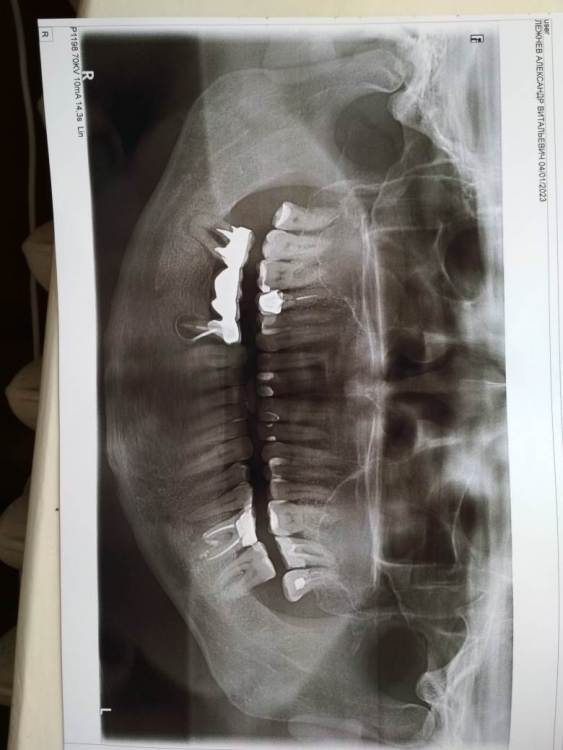

Александр Ле Опубликовано 8 августа, 2023 Поделиться Опубликовано 8 августа, 2023 На десне , под зубом на котором закреплен мост - свищ. Есть ли возможность снять мост, вылечить зуб и поставить мост обратно? В Ярославле это делают? Ссылка на комментарий

kuziy12 Опубликовано 9 августа, 2023 Поделиться Опубликовано 9 августа, 2023 Доброго времени суток. Мост нужно снимать. Зубы, которые под мостом - процентов 99, что удалять. 4.7 из- за пародонтальных проблем(грубо говоря - проблема с костью и десной), зуб 4.5 из за очага воспаления на верхушки корня. 1 Ссылка на комментарий

Doc Опубликовано 9 августа, 2023 Поделиться Опубликовано 9 августа, 2023 В данном случае шансов нет даже теоретических. Увы. Удалять и имплантацию делать, либо съемный протез. 1 Ссылка на комментарий

kuziy12 Опубликовано 9 августа, 2023 Поделиться Опубликовано 9 августа, 2023 11 минут назад, Александр Ле сказал: Спасибо. А костной ткани достаточно для имплантации? А что будет, если все оставить как есть? Для оценки костной ткани нужно делать КТ. Здесь, скорее всего, разумным вариантом будет удаление зубов, подождать полного заживления(2-3 месяца) и только потом обращаться на консультацию к имплантологу. Бездействие может привести к печальным последствиям - на зубе 4.5 инфекции будет развиваться и когда-нибудь случиться периостит(флюс в простонародье или отек). Я предполагаю, что у вас уже есть неприятный запах из полости рта. Скоро появится подвижность зубов и моста(если уже ее нет). Ссылка на комментарий